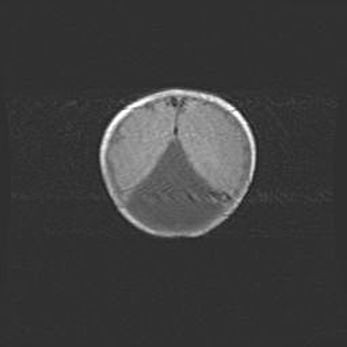

Ликворная киста прозрачной перегородки.

Возраст: 11 дней

Вес: 3400 г

Пол: мужской

Окружность головы: 34 см

Срок гестации: 40 недель

Киста прозрачной перегородки – это полостное образование в виде капсулы с плотными стенками, наполненное жидкостью, и расположенное в полости головного мозга. Стенки кисты прозрачной перегородки состоят из клеток паутинной оболочки, а наполнена она ликвором – мозговой жидкостью.